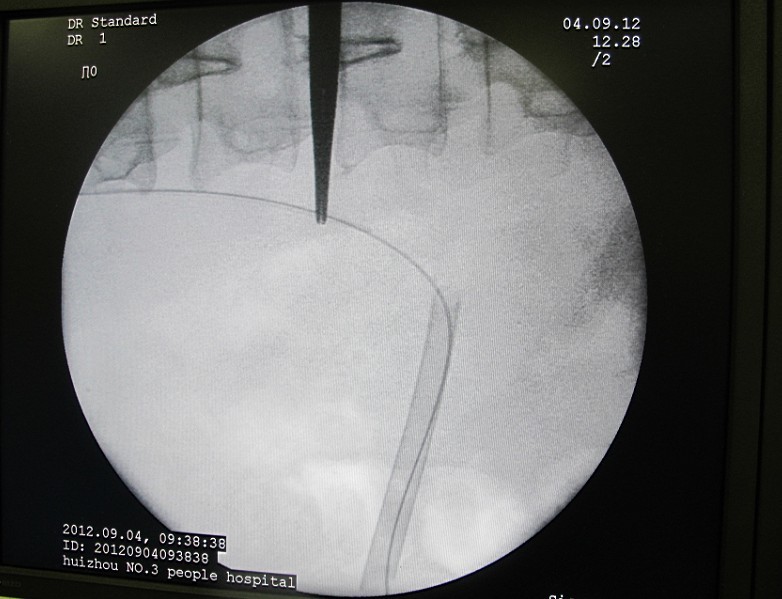

5术前和术后C臂透视可见通道异常精确自中小盏抵达肾盂出口。对比可以清晰的看到结石已完全清除。

6 结石没了,置导丝入膀胱准备放置双J管。